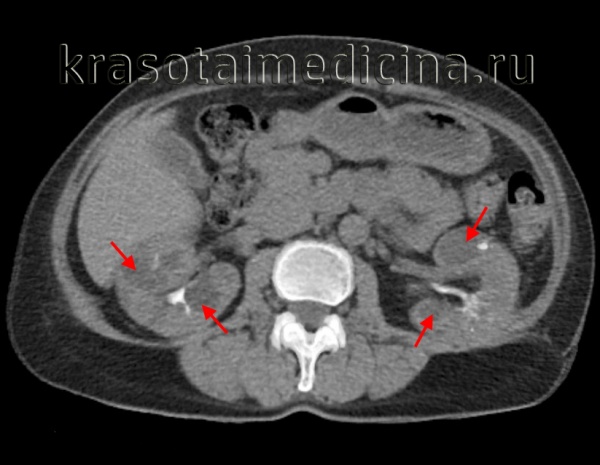

(Слева) КТ без контрастирования, аксиальная проекция: поликистозное поражение почек и печени. В то время как большинство кист почки гиподенсные, периферические кисты левой почки - гиперденсные, сравнимые по плотности с геморрагическими кистами.